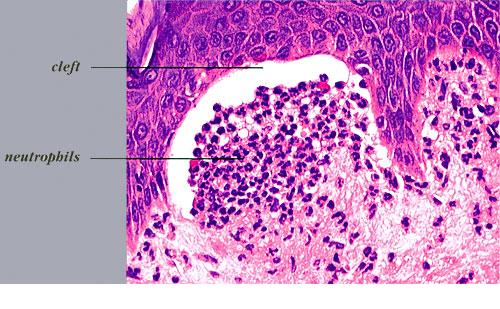

. The typical histologic features are best observed in erythematous skin adjacent to early blisters. In these zones, neutrophils accumulate at the tips of dermal papillae. With an increase in size to microabscesses, a significant admixture of eosinophils may be noted. As microabscesses form, a separation develops between the tips of the dermal papillae and the overlying epidermis; thus, the early blisters are multiloculated . The presence of fibrin in the papillae may give them a bluish appearance. Within 1 to 2 days, the rete ridges lose their attachment to the dermis, and the blisters then become unilocular  and clinically apparent. At this time, the characteristic papillary microabscesses may be observed at the blister periphery. For this reason, the inclusion of perivesicular skin in the biopsy specimen is of

utmost value. The papillary dermis beneath the papillae may have a relatively intense inflammatory infiltrate of neutrophils and some eosinophils. Many neutrophils may exhibit leukocytoclasis. Subjacent to this, a perivascular infiltrate composed of lymphocytes, neutrophils, and eosinophils may be apparent. the diagnostic finding of papillary microabscesses may not be present in all patients. Apoptotic keratinocytes may be noted above the papillary microabscesses.